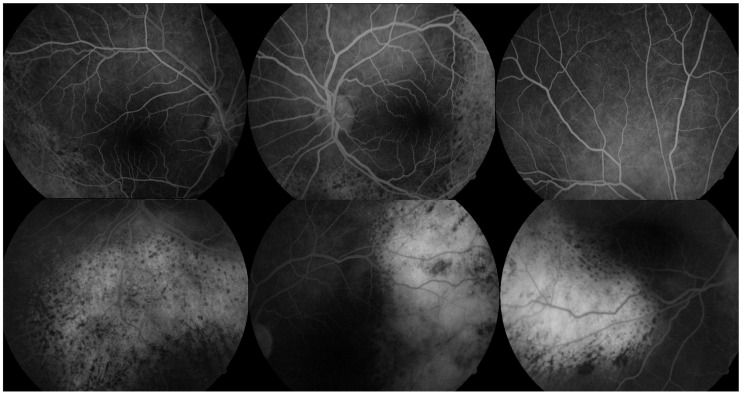

Bilateral diffuse uveal melanocytic proliferation (BDUMP) is a rare paraneoplastic syndrome characterized by bilateral uveal melanocyte proliferation and progressive visual disturbance. While most commonly associated with solid tumors, its occurrence in hematologic malignancies is exceedingly rare. We report a case of BDUMP in a 64-year-old male recently diagnosed with chronic myelomonocytic leukemia (CMML), who presented with subacute, painless bilateral blurred vision. Multimodal imaging revealed suggestive features of BDUMP, including orange-red subretinal patches, retinal pigment epithelium mottling, and diffuse choroidal thickening, consistent with early structural involvement despite preserved central vision. No intraocular mass or signs of inflammation were observed. The patient did not receive specific treatment for BDUMP, and visual acuity remained stable during follow-up. This case underscores the importance of considering BDUMP in the differential diagnosis of bilateral visual symptoms in patients with hematologic malignancies. Although rare, BDUMP may occur in the context of CMML. Recognition through multimodal imaging and interdisciplinary collaboration is essential, and further research is needed to clarify its pathogenesis and improve management strategies.